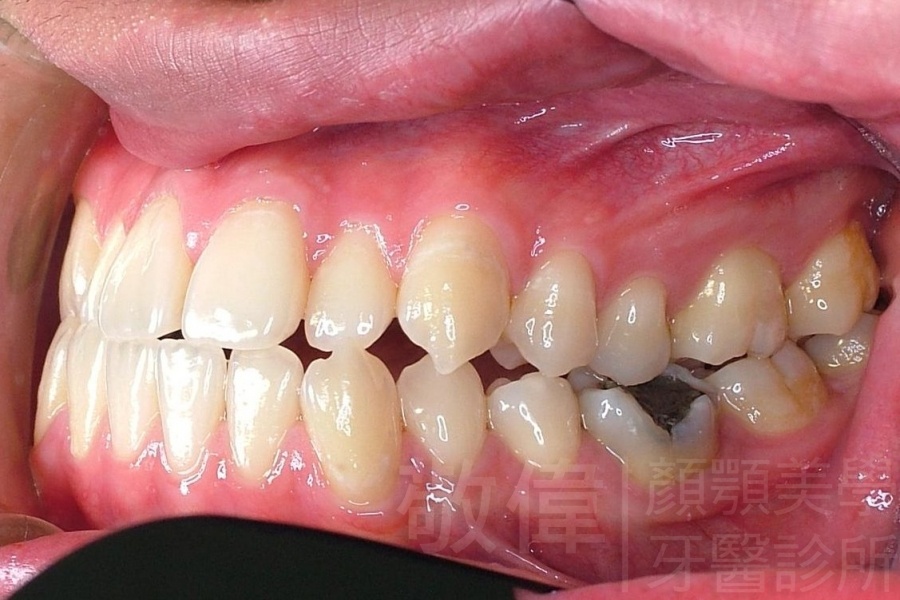

齒顏矯正/戽斗、亂牙、爛牙,變身 免植牙的健牙美女

<個案說明>

變臉矯正,原來戽斗妹跟大歪臉變成自信正妹

經由本院3D數影X光影像儀分析、與3D齒顎顏矯正技術,再配合口腔顎面正顎專科醫師施以正顎手術治療,雙方共同合作,使患者臉部外觀有很好的改善,大歪變小歪,產生了天南地北的大改變,她的人生也整個變得不一樣。